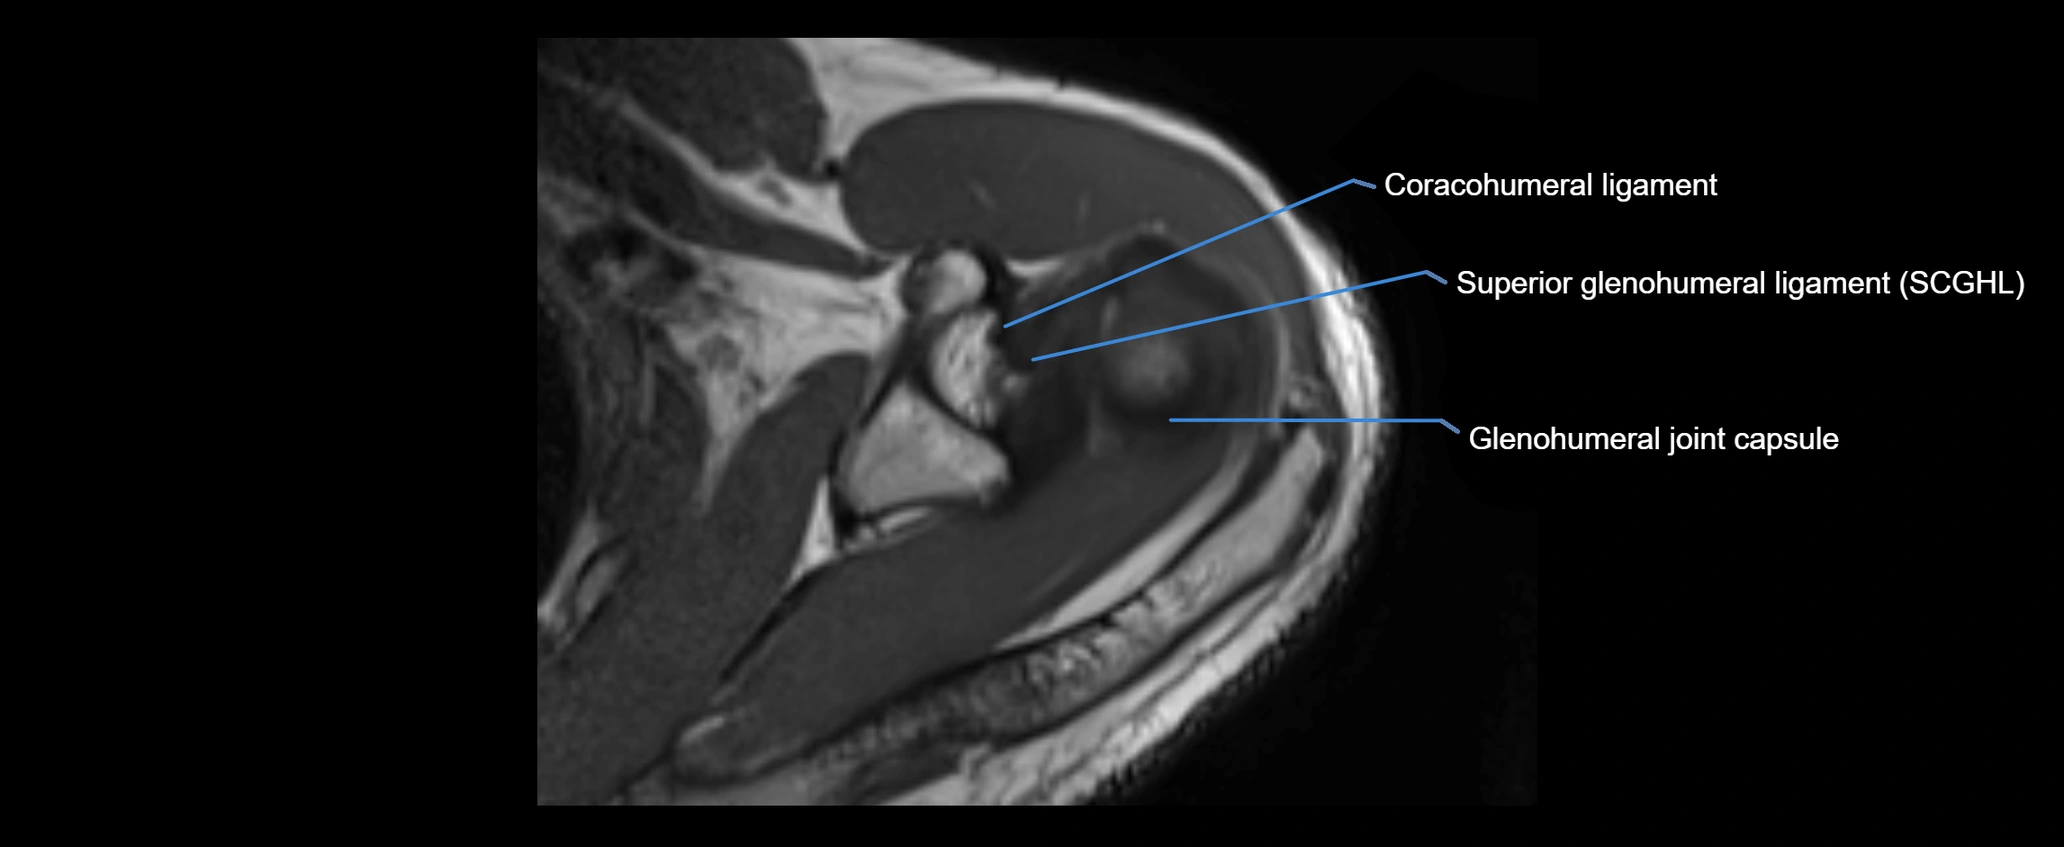

MRI images

image